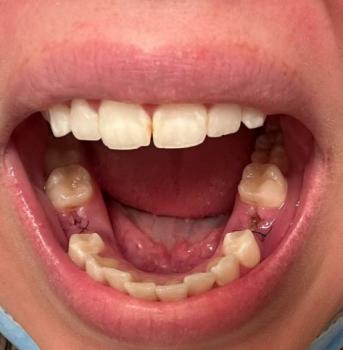

The image shows a treated tooth with sutures placed on the surrounding gum tissue. The area appears reddened and swollen, indicating recent root canal–related surgical treatment or management of an infection at the root area. The presence of sutures suggests that the infection required surgical access, drainage, or gum repair.

This is a normal appearance shortly after treatment but requires close monitoring.

This case shows post-root canal surgical healing with sutures, commonly used to control deep infection. With proper follow-up and care, the prognosis is usually good.